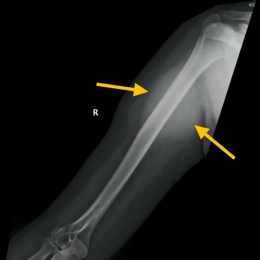

Radiographic imaging is used to help form a diagnosis. These include X-Ray, MRI, CT and Bone Scans

An example of an MRI is shown.